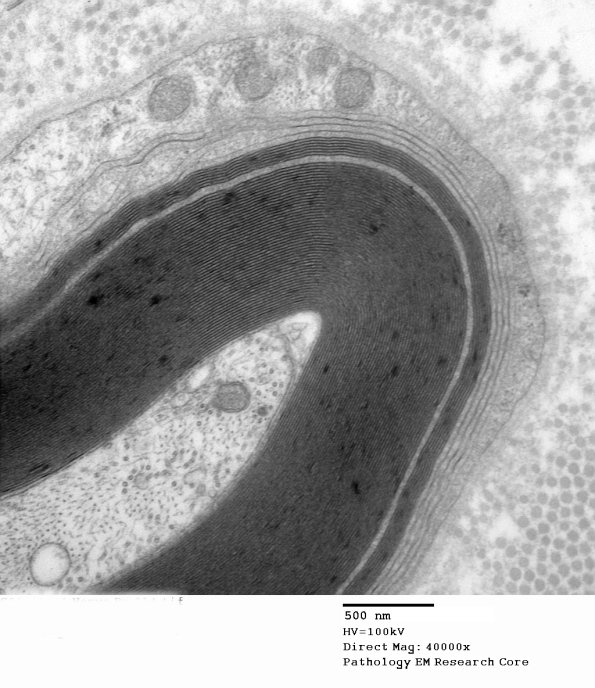

Some define the significance of WSM based on the number of lamellae involved but we have not found WSM to be a normal finding in nerve biopsies but is not pathognomonic of anti-MAG neuropathy either. (electron micrograph)